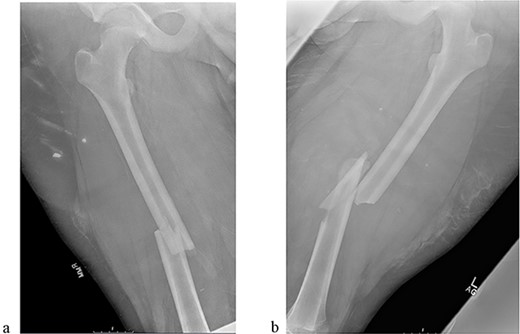

The patient tolerated the procedure well and recovered uneventfully. He was noted to have circumferential osseous healing at 1 year and underwent bilateral femur IMN removal 1.5 years postoperative without complication (Figs 4a–d and 5a–d).

(a) Right femur AP radiograph. (b) Right femur lateral radiograph. (c) Left femur AP radiograph. (d) Left femur lateral radiograph.